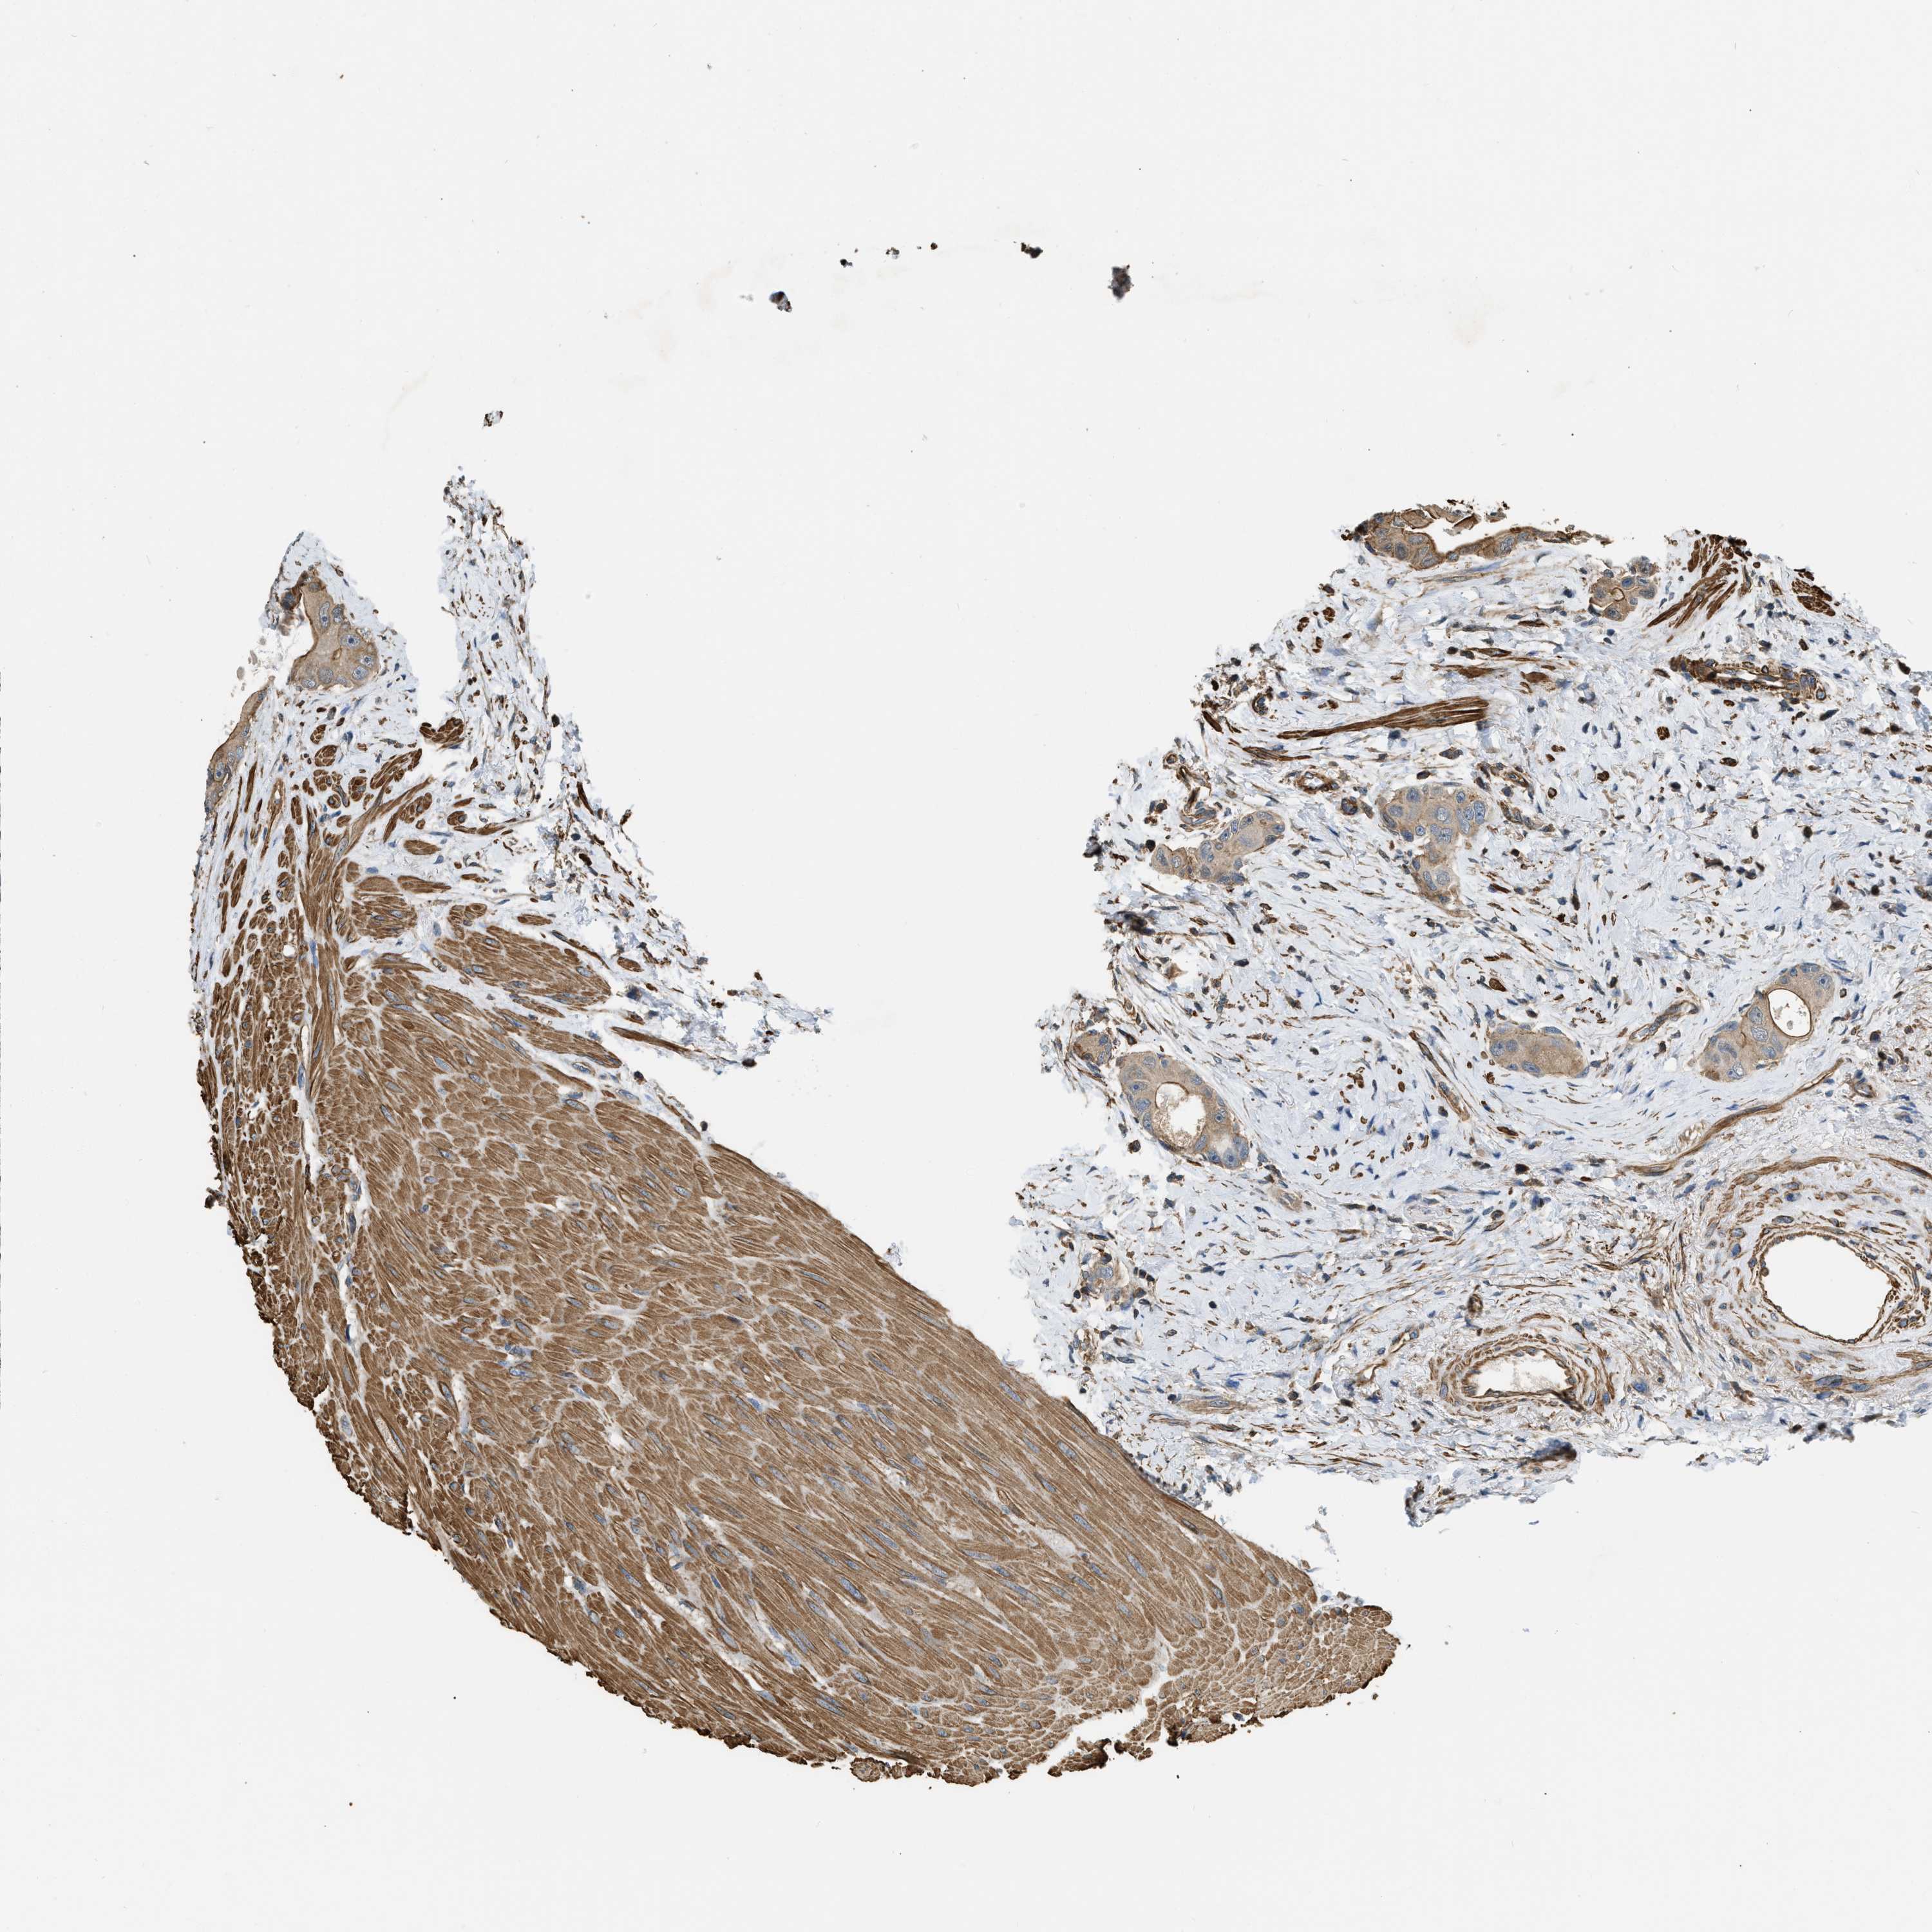

CANCER COLORECTAL CANCER Show tissue menu

Colorectal cancer

Human cancer

Colon adenocarcinoma

Rectum adenocarcinoma